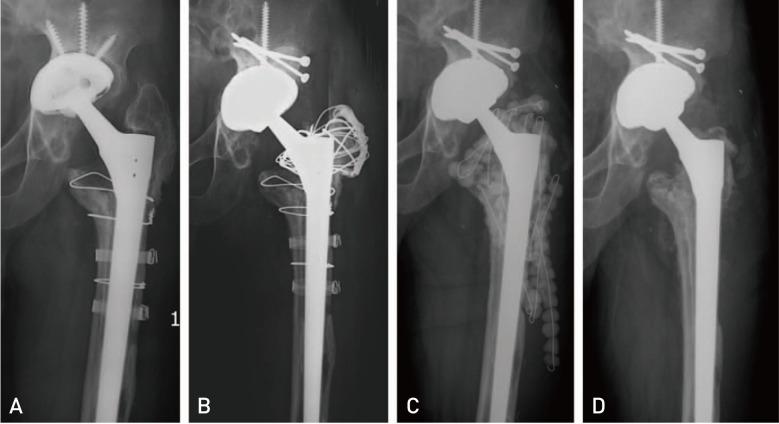

The treatment of infected revision total hip arthroplasty (THA) is very challenging due to retained revision prosthesis, poor bone stock and soft tissue condition derived from previous revision surgeries, and comorbidities. The purpose of this study was to investigate the effectiveness and short-term outcomes of aggressive debridement and use of antibiotic-loaded cement beads with retention of the prosthesis for acute delayed or late infection of revision THAs.

Ten consecutive patients with symptoms or signs of less than one-week evolution and well-fixed prostheses, were treated with this procedure and a postoperative course of organism-specific antibiotics for a minimum of 6 weeks. All hips presented with acute delayed or late infection of revision THAs. Patients with a mean age of 68.1 years (range, 59-78 years) underwent an average of 1.9 previous revision THAs (1-4) before the index surgery. The minimal follow-up was 2 years with a mean of 46.2 months (range, 24-64 months).

There were 8 cures (80.0%) and 2 failures with no mortality during the study period. The 2 failures involved the same and resistant bacteria implicated in the primary infection (methicillin-resistant and , respectively). The mean Harris hip score was 65.2 (range, 26-83) and the mean visual analogue scale was 2.6 (range, 1-4) at final follow-up.

由于翻修假体的存留、既往翻修手术导致的骨量不佳和软组织条件差以及合并症,感染性翻修全髋关节置换术(THA)的治疗极具挑战性。本研究的目的是探讨积极清创并使用载抗生素骨水泥珠粒同时保留假体治疗翻修THA急性延迟感染或晚期感染的有效性和短期结果。

连续10例有症状或体征且病程少于1周且假体固定良好的患者接受了该手术,并术后使用针对病原体的抗生素至少6周。所有髋关节均表现为翻修THA的急性延迟感染或晚期感染。患者平均年龄68.1岁(范围59 - 78岁),在本次手术前平均接受过1.9次(1 - 4次)翻修THA。最短随访时间为2年,平均46.2个月(范围24 - 64个月)。

研究期间有8例治愈(80.0%),2例失败,无死亡病例。2例失败涉及与初次感染相同且耐药的细菌(分别为耐甲氧西林金黄色葡萄球菌和表皮葡萄球菌)。末次随访时Harris髋关节平均评分为65.2(范围26 - 83),视觉模拟评分平均为2.6(范围1 - 4)。